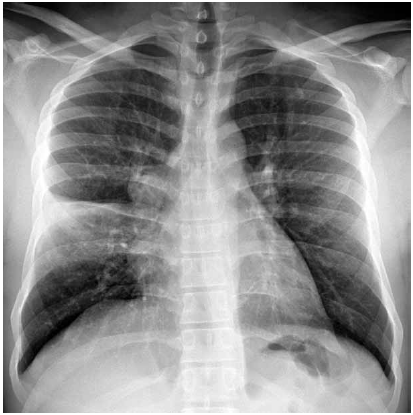

Homem de 24 anos de idade, sem antecedentes patológicos, apresenta-se à unidade básica de saúde com quadro de febre, dispneia e tosse com expectoração amarelada há 3 dias. Ele nega náuseas, vômitos, dor abdominal, diarreia, uso de medicamentos, tabagismo, etilismo ou uso de drogas. Exame físico: consciente, corado, hidratado e anictérico; PA: 115 x 75 mmHg, FC: 98 bpm, T: 38,6 ºC, FR: 16 ipm e SatO2: 96%; abdome: indolor; exame cutâneo e extremidades sem alterações relevantes. A radiografia realizada é mostrada a seguir.

Com essas informações, é correto afirmar: